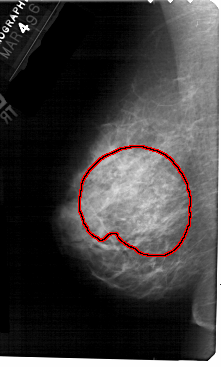

FILE: A_1559_1.LEFT_MLO.OVERLAY

TOTAL_ABNORMALITIES 1

ABNORMALITY 1

LESION_TYPE CALCIFICATION TYPE AMORPHOUS DISTRIBUTION REGIONAL

ASSESSMENT 4

SUBTLETY 3

PATHOLOGY BENIGN

TOTAL_OUTLINES 1

BOUNDARY